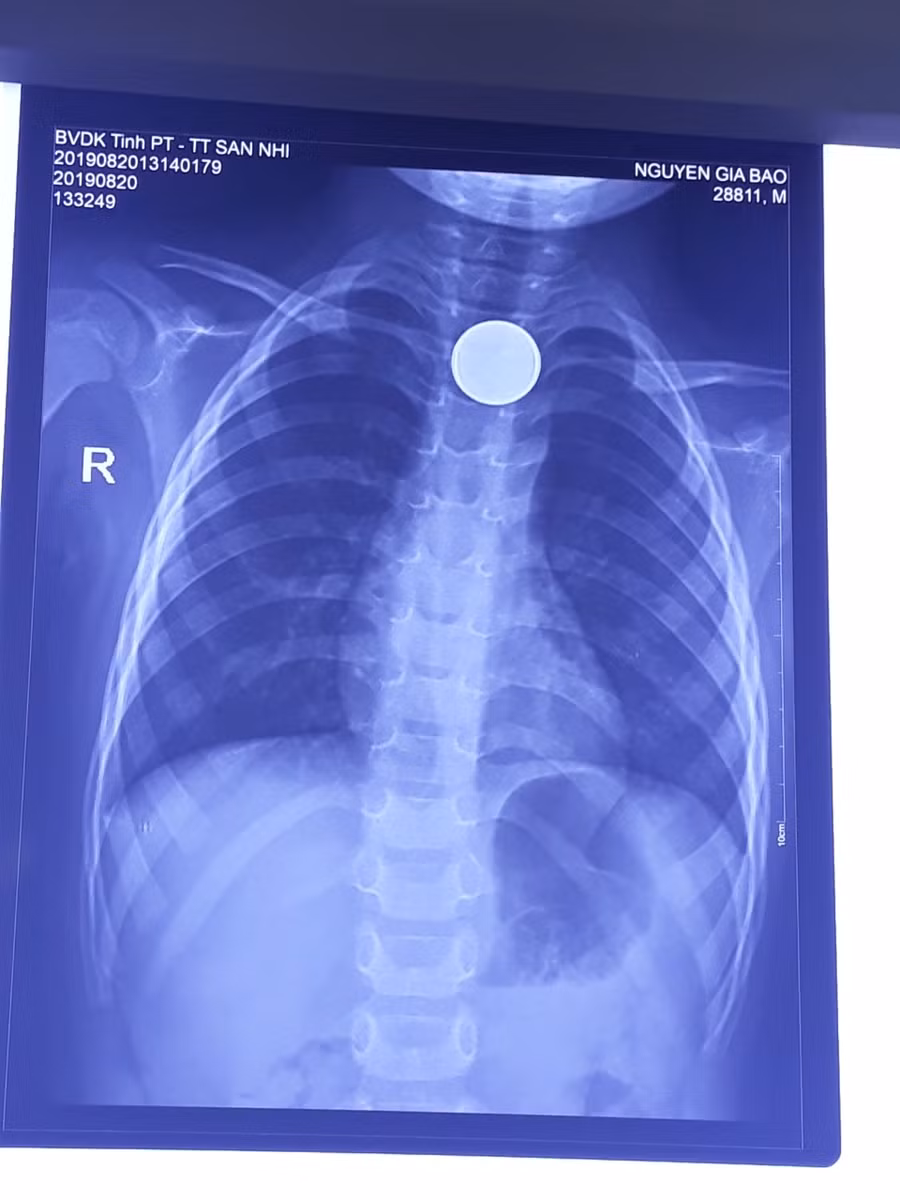

Chụp Xquang cho thấy xuất hiện hình ảnh dị vật là 1 đồng xu mắc ở 1/3 phần trên của thực quản của trẻ. Các bác sĩ của trung tâm đã phối hợp với các BS ngoại khoa – Trung tâm khám chữa bệnh chất lượng cao – BV Đa khoa tỉnh Phú Thọ để tiến hành nội soi can thiệp gắp dị vật ra khỏi cơ thể.

| Phim chụp hình ảnh dị vật (BVCC) |